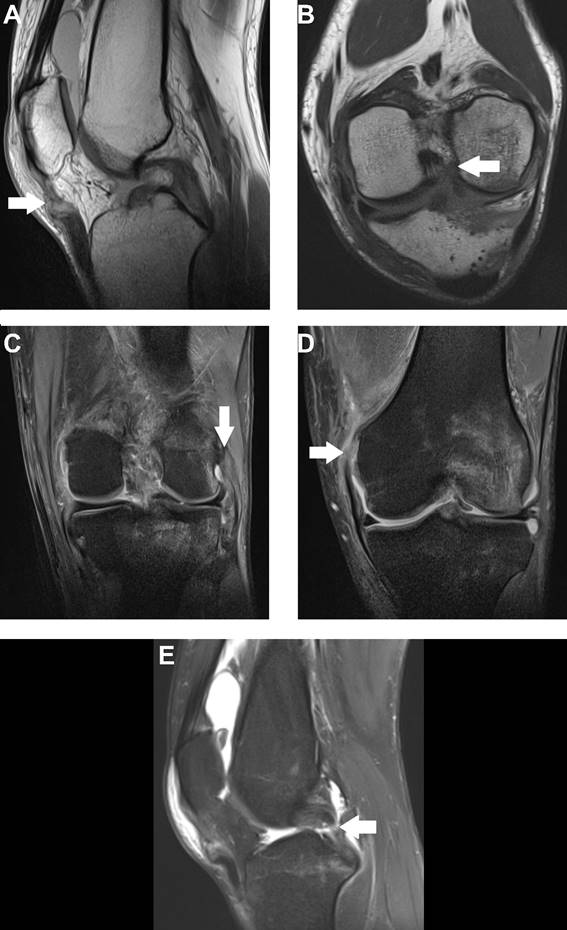

A 27-year-old man experienced a left knee sprain 15 days ago during a football game. Physical examination with knee tests was not performed at the time of trauma due to pain, only joint swelling was detected. Magnetic resonance imaging (MRI) detected a complete rupture of the anterior cruciate ligament and the proximal insertion of the medial collateral ligament, a partial rupture of the posterior cruciate, lateral collateral and patellar ligaments (Figure), and peripheral rupture of the posterior horn of the lateral meniscus. The patient underwent surgery for patellar ligament 50 days after the MRI, followed by 30 sessions of physiotherapy, reporting pain improvement. Seven months later he had another surgery, but, this one, for anterior cruciate ligament correction. Since the second surgery, he is improving the mobility and pain with physiotherapy.

Figure:  DP sagittal section MRI (A) detecting patellar ligament partial tear (white arrow). T2 oblique section MRI (B) demonstrating anterior cruciate ligament complete tear (white arrow). DP FAT SAT coronal section MRI showing lateral collateral ligament partial tear (C - white arrow) and medial collateral ligament complete tear (D - white arrow). Sagittal T2 FAT SAT section MRI (E) detecting posterior cruciate ligament partial tear (white arrow)